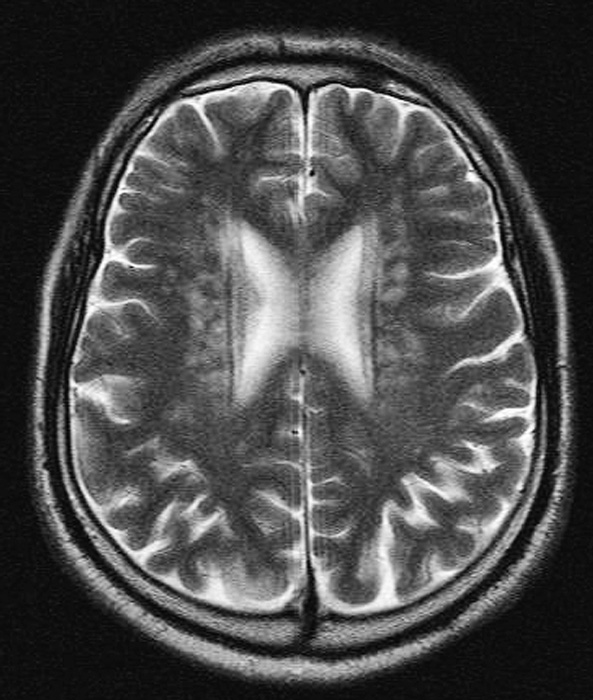

Typical Grade 5 case, a 61-year-old male who had many T2-elongated spots whose borders were connected in the basal ganglia (Arrow head).